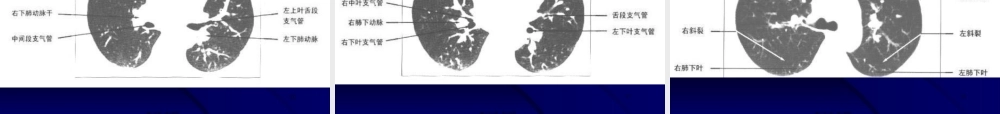

1呼吸系统(hūxīxìtǒnɡ)影像学第一页,共一百页。2第一(dìyī)部分正常胸部CT解剖一、正常胸部纵隔窗CT解剖第二页,共一百页。3胸锁关节层面(平扫)第三页,共一百页。4胸锁关节层面(增强)第四页,共一百页。5主动脉弓上层面(平扫)第五页,共一百页。6主动脉弓上层面(平扫)第六页,共一百页。7主动脉弓层面(平扫)第七页,共一百页。8气管分叉层面(平扫)第八页,共一百页。9气管分叉层面(增强)第九页,共一百页。10第十页,共一百页。11左心房层面(平扫)第十一页,共一百页。12左心房层面(增强)第十二页,共一百页。13左、右心房层面(增强)第十三页,共一百页。14四腔心层面(平扫)第十四页,共一百页。15心室层面(平扫)第十五页,共一百页。16二、正常胸部(xiōnɡbù)肺窗CT解剖第十六页,共一百页。17气管分叉层面第十七页,共一百页。18右上叶支气管层面第十八页,共一百页。19左主支气管中段层面第十九页,共一百页。20第二十页,共一百页。21右中叶支气管开口层面第二十一页,共一百页。22显示双侧斜裂层面第二十二页,共一百页。23显示各肺叶层面第二十三页,共一百页。24下肺层面第二十四页,共一百页。25三、肺段图谱(túpǔ)第二十五页,共一百页。26第二十六页,共一百页。27第二十七页,共一百页。28第二十八页,共一百页。29第二十九页,共一百页。30第三十页,共一百页。31第三十一页,共一百页。32第三十二页,共一百页。33第三十三页,共一百页。34第二部分呼吸系统(hūxīxìtǒnɡ)基本病变的影像学表现第三十四页,共一百页。35腔内性:肿瘤、异物、炎症、结核等腔外性:淋巴结增大压迫部分(bùfen)阻塞:阻塞型肺气肿完全阻塞:阻塞型肺不张第三十五页,共一百页。361.阻塞性肺气肿:见于慢支及支气管哮喘。2.影像表现(biǎoxiàn):3.肺野透过度增加;4.肺纹理稀疏变细,可见肺大泡;5.横膈低平,活动度减低;6.胸廓呈桶状,肋间隙增宽;7.心影狭长呈垂位心型,心后间隙增宽;第三十六页,共一百页。37•肺不张:肺叶(fèiyè)支气管完全性阻塞的后果•肺不张的共同特点:肺体积缩小,密度增高;叶间裂移位;肋间隙变窄;肺门及纵隔不同程度向患侧移位;邻近肺叶代偿性肺气肿。第三十七页,共一百页。38二、阻塞性肺不张右肺下叶不张右中叶(zhōngyè)肺不张第三十八页,共一百页。39二、阻塞性肺不张左上叶中央(zhōngyāng)型肺癌左肺上叶不张第三十九页,共一百页。40•一、渗出性病变与实变(e...